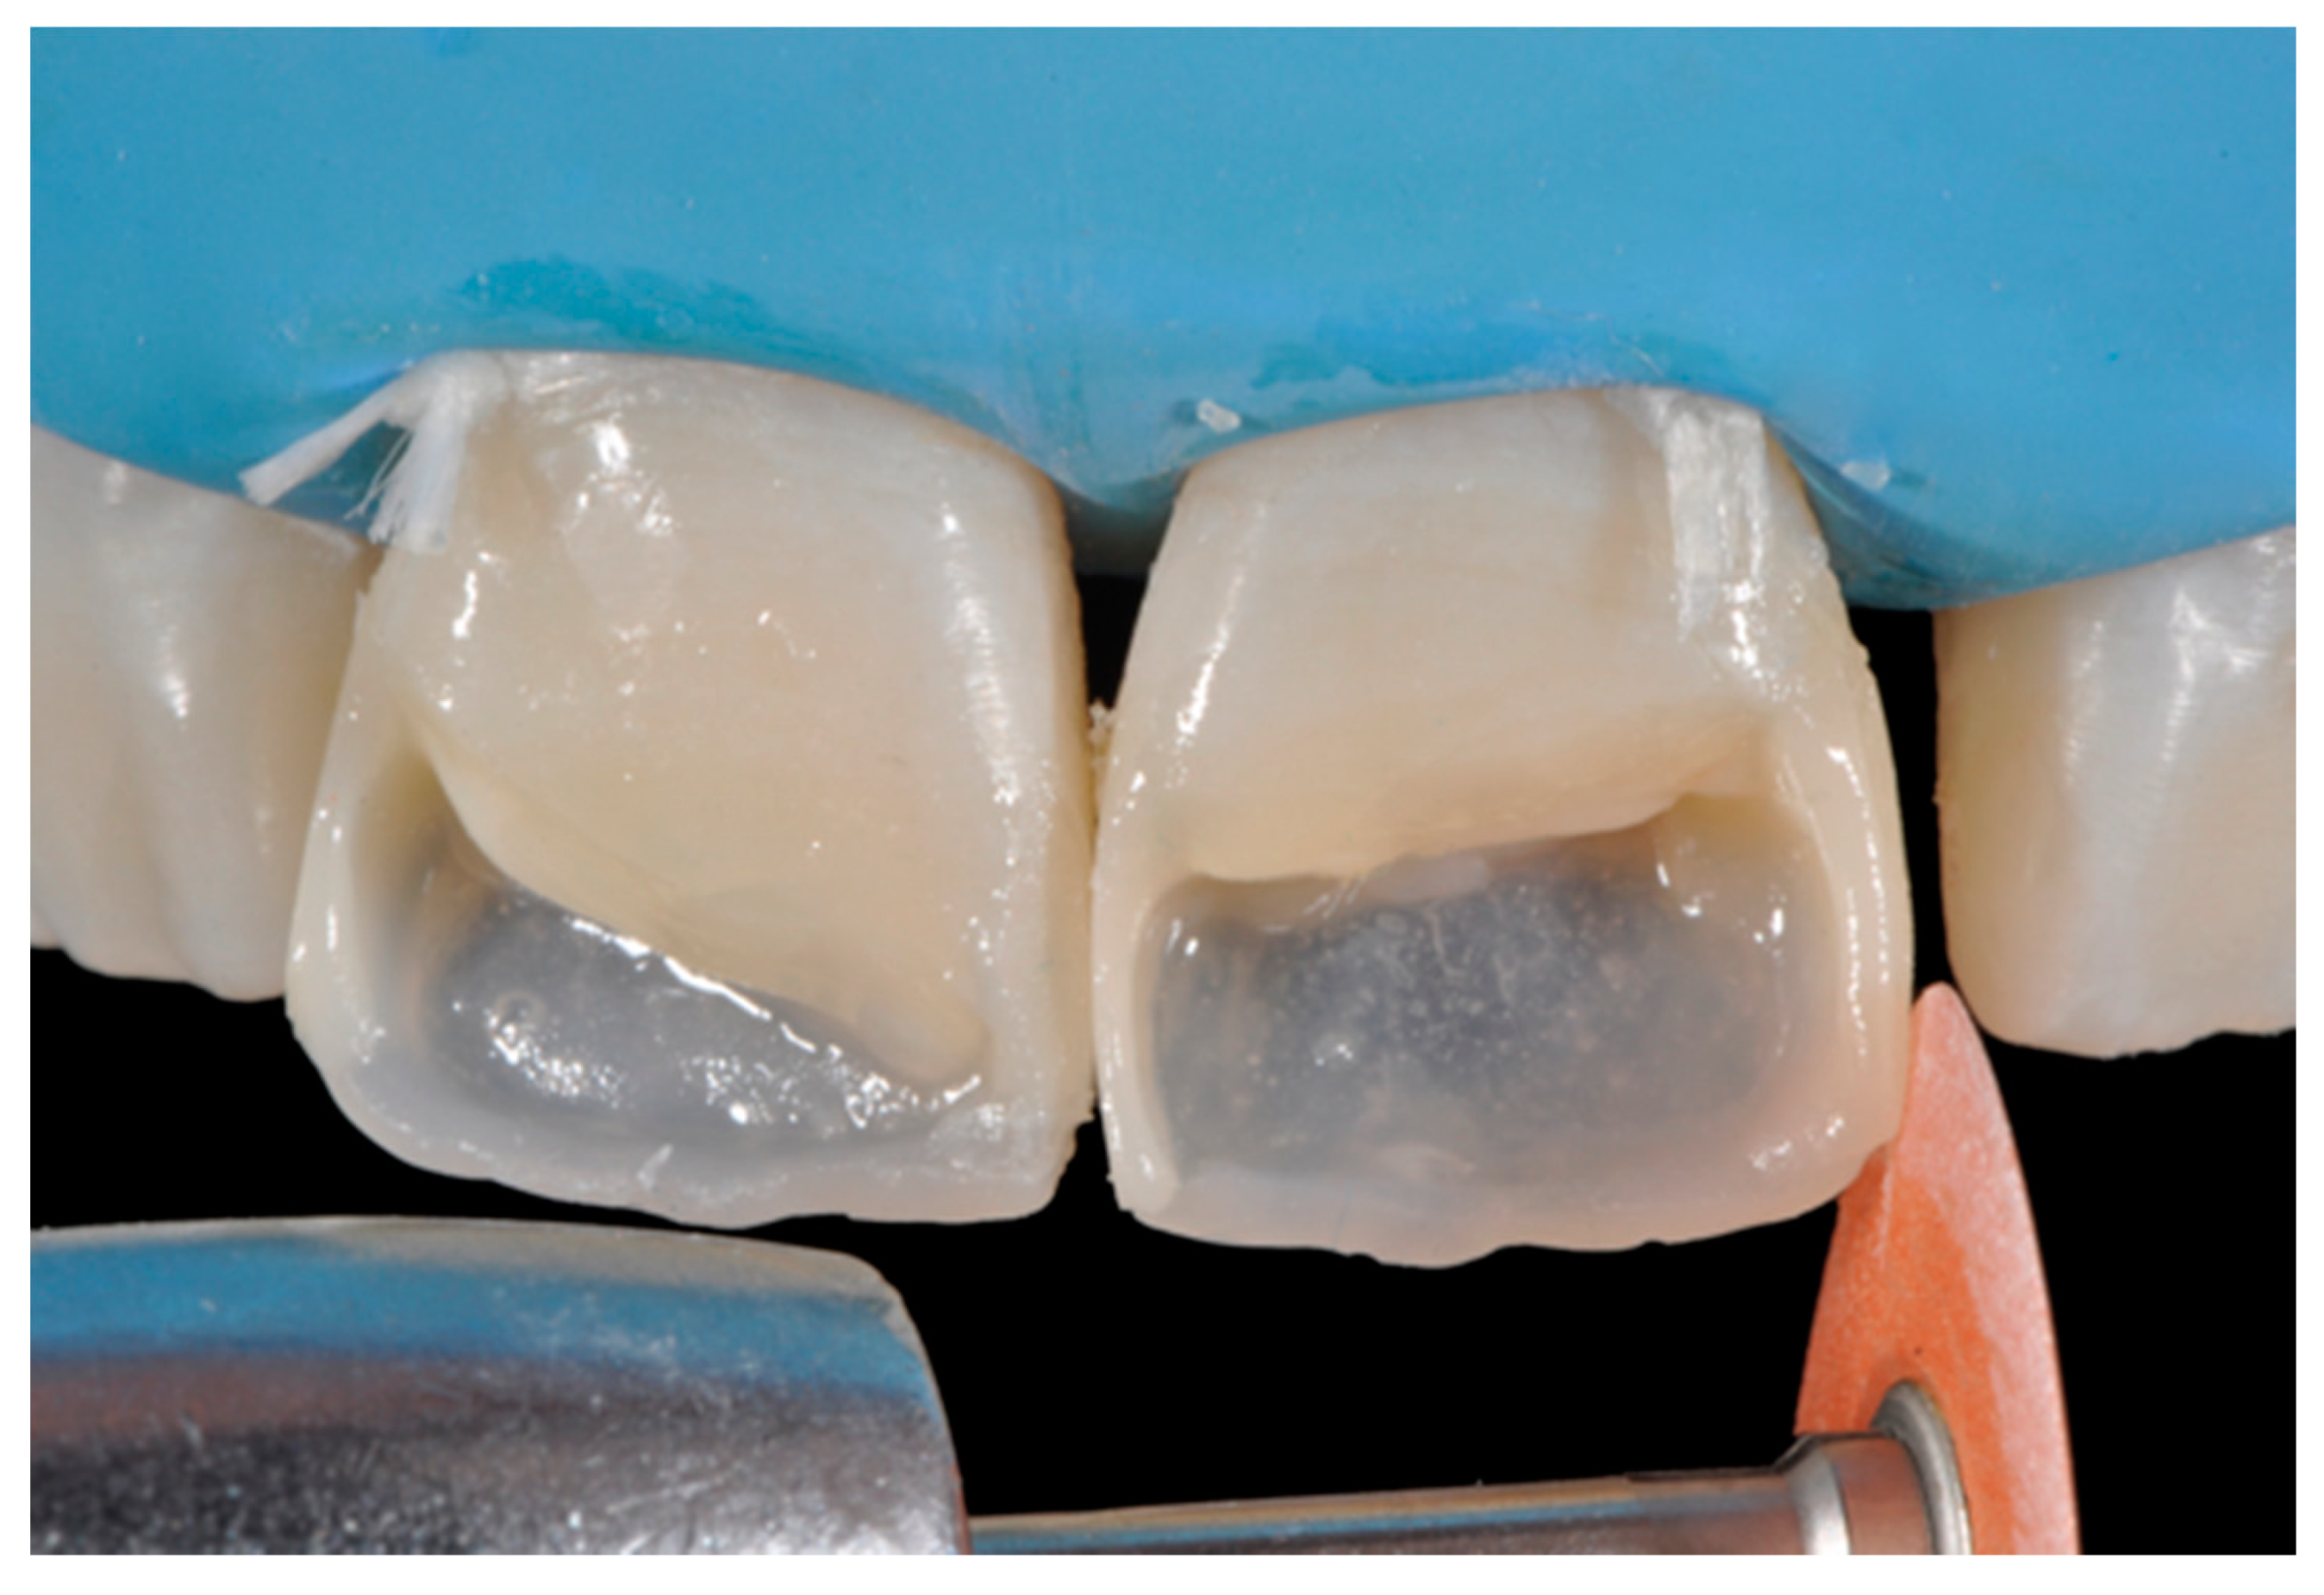

Once completed, the two frames (Clearfil Majesty ES-2, A1E, A2D, Kuraray Noritake Dental, Tokyo, Japan) showed internal and external excesses that were reduced using diamond burs and discs (Figure 33 and Figure 34) strictly following the procedure described in Section 2.1.2 of present article. Excesses were removed from the distal-incisal angle of #2.1 allowing therefore to obtain the desired translucency. After silane application and bonding procedure (Figure 35) as described in Section 2.1.2, restorations were completed (Figure 36 and Figure 37). They both show satisfactory clinical integration 1.5 years post-operative (Figure 38 and Figure 39).

Figure 33.

Frame imprecisions are corrected by reducing interproximal wall from the internal side. Reprinted from Restauri diretti nei settori anteriori, G. Paolone, S. Scolavino, © 2021, with permission from Quintessence Publishing Italy.

Figure 34.

Frame is also trimmed reducing external outline. Reprinted from Restauri diretti nei settori anteriori, G. Paolone, S. Scolavino, © 2021, with permission from Quintessence Publishing Italy.

Figure 35.

The modified frames treated with silane coupling agent and adhesive, ready for layering of dentinal body. Reprinted from Restauri diretti nei settori anteriori, G. Paolone, S. Scolavino, © 2021, with permission from Quintessence Publishing Italy.